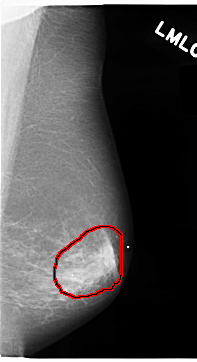

C_0074_1.LEFT_MLO

LEFT_MLO LINES 4704 PIXELS_PER_LINE 2552 BITS_PER_PIXEL 12 RESOLUTION 50 OVERLAY

FILE: C_0074_1.LEFT_MLO.OVERLAY

TOTAL_ABNORMALITIES 1

ABNORMALITY 1

LESION_TYPE MASS SHAPE IRREGULAR MARGINS SPICULATED

ASSESSMENT 5

SUBTLETY 5

PATHOLOGY MALIGNANT

TOTAL_OUTLINES 1

BOUNDARY